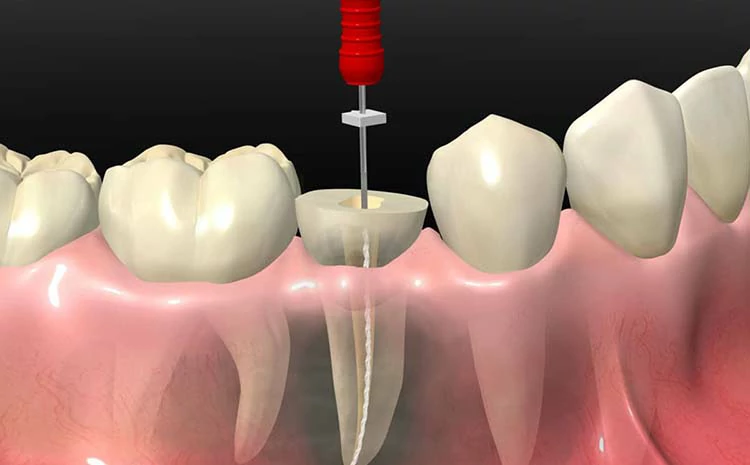

2- علاج قناة الجذر

هو الخيار المثالي لـ علاج خراج الاسنان، وفيه يتم إزالة أنسجة لب السن أو الضرس المتضرر؛ من أجل الاحتفاظ بالسن وعدم خلعه.

خلال الإجراء، يقوم الطبيب بإعطاء المريض حقنة مخدرة موضعية في اللثة؛ لتخدير أجزاء الفك والفم المتضررة من الخراج، بعد ذلك يقوم الطبيب بإزالة اللب المصاب، ويقوم بتنعيم الجزء الداخلي من قنوات اللب، ثم يعمل على حشو السن بمادة حشو معينة.